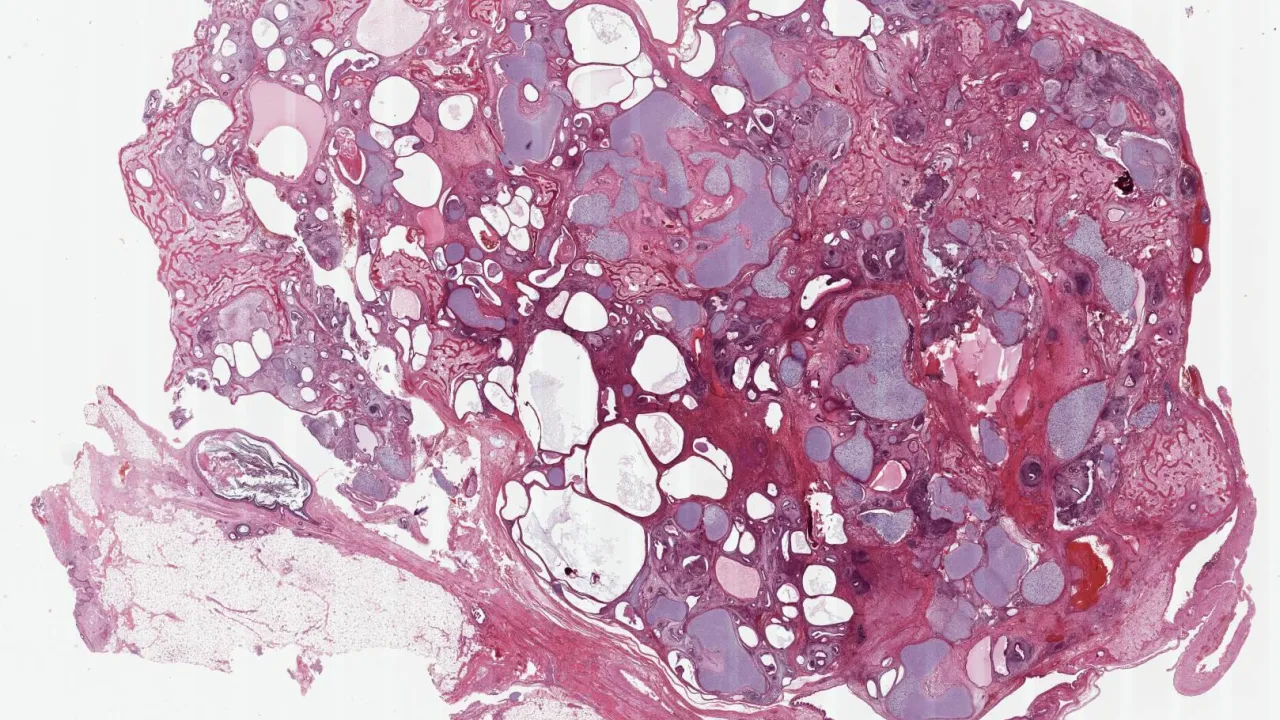

Ovary, Immature teratoma